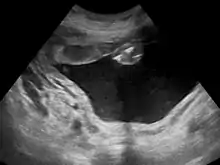

Polyhydramnios is a medical condition describing an excess of amniotic fluid in the amniotic sac. It is seen in about 1% of pregnancies.[1][2][3] It is typically diagnosed when the amniotic fluid index (AFI) is greater than 24 cm.[4][5] There are two clinical varieties of polyhydramnios: chronic polyhydramnios where excess amniotic fluid accumulates gradually, and acute polyhydramnios where excess amniotic fluid collects rapidly.